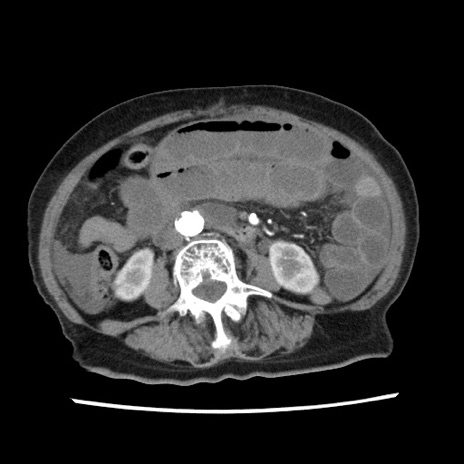

症例1(横断像)

【症例】80歳代女性

【主訴】腹痛

【現病歴】8時間前から腹痛あり来院。

【既往歴】糖尿病、脂質異常症、子宮体癌にて子宮全摘術

【身体所見】意識清明・会話良好だが腹痛で苦悶様、全腹部にわたって反跳痛と圧痛あり

【データ】WBC 13600、CRP 0.14、LDH 224、CK 90